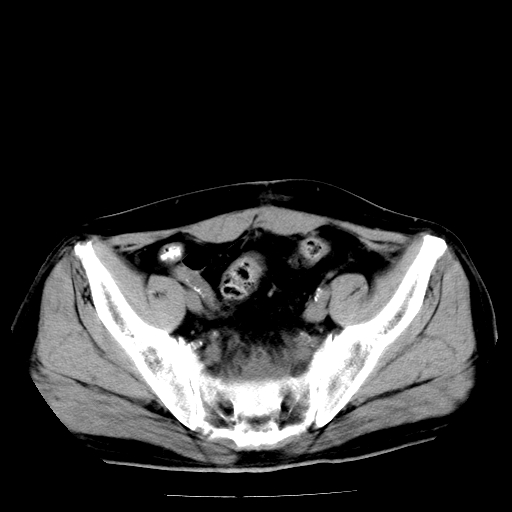

男,66岁,直肠癌术后一个月,化疗前ct检查。

前列腺大,直肠壁厚,造瘘术后

直肠癌造瘘术后改变,周围淋巴结转移

前列腺肥大

直肠癌造瘘术后改变,盆腔多发淋巴结转移

直肠癌造瘘术后改变,直肠周围软组织增厚,盆腔多发淋巴结转移。前列腺肥大。

结肠造瘘术后。

直肠癌周围浸润。

前列腺肥大。